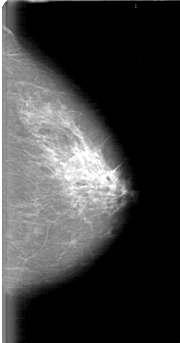

D_4064_1.LEFT_CC

LEFT_CC LINES 5131 PIXELS_PER_LINE 2686 BITS_PER_PIXEL 12 RESOLUTION 43.5 NON_OVERLAY